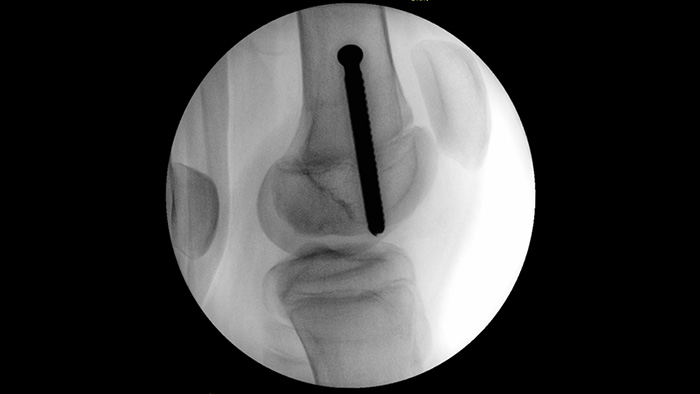

MetalSmart automatically excludes metal artifacts, caused by metal implants, to provide higher image quality and efficient dose control during orthopedic procedures and patients with metal implants, compared to systems without metal exclusion. BodySmart promotes first-time-right imaging and dose efficiency by automatically adapting the measuring field to the area of interest.

When setting pedicle screws for a spinal fusion or fracture repair, reducing technical distractions and discussions can help surgical teams remain focused on the patient. With Unify workflow’s navigation aids, surgical teams experienced smoother interactions and less miscommunication in a usability study.1